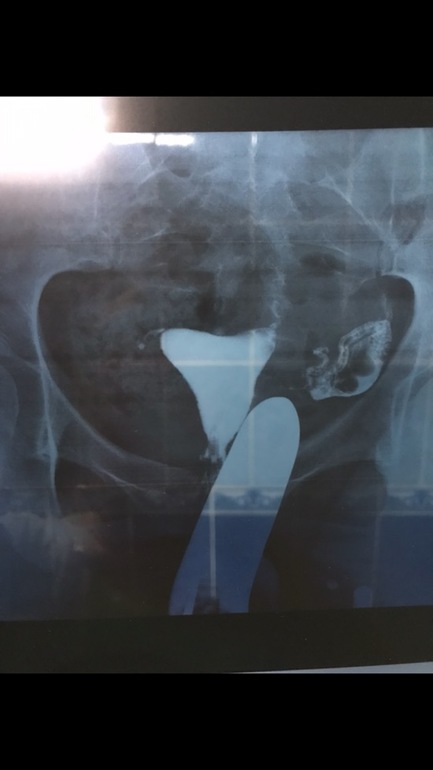

Гсг

Чисто для себя хочу понять где скопилась эта жидкость и где примерно спайки эти?!😏

Так я же Вам объясняла...да Вы и сами уже в курсе. Спайки там, где застряла жидкость у Вас. Застревала в трубе, значит там спайки были, прошла потом из трубы, значит "пробили" жидкостью. Не растеклась свободно вышедшая из трубы жидкость, значит спайки при входе в трубу. Повлияет ли на зачатие, Вам достоверно никто не скажет. В принципе, на данный момент труба проходима, это радует. Наверное стоит постараться в сл цикле и посмотреть что будет. На тот момент уже наверняка и с доктором встретитесь, он конкретно все разложит по буквам.

Ну спайки, это и есть воспаление, его она и увидела. Насчёт сосиски...хм...у Вас вроде извилистая труба...мало на сосиску похожа...может восприятие врача...

Она сказала видишь труба у тебя узкая а потом расширилась? И идёт толстая как сосиска

Толстая труба чем плоха? Возможно она видит, что она расширилась за счёт отёчности стенок вследствии воспаления? Я например вижу контраст на снимке, да, в определенной части трубы его больше, соответственно, труба шире... но это не указывает на воспалённые стенки как таковое. Возможно есть какие нюансы в прочтении, Вы бы у врача попросили Вам объяснить поподробнее, почему она так думает.

А она мне сразу, видишь труба тонкая в начале? А потом толстая это воспалённая. И все что она сказала